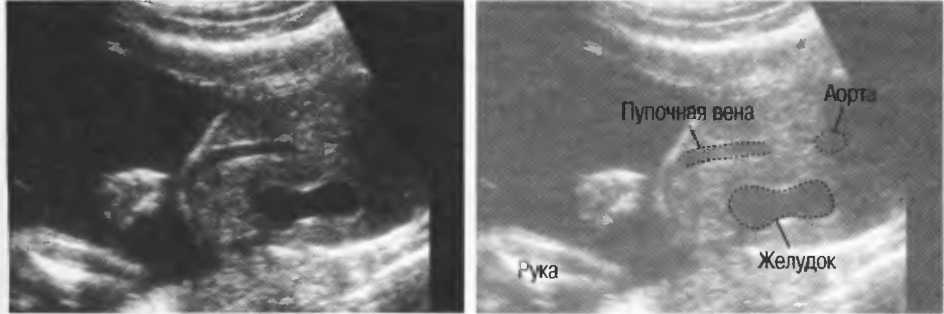

Рис.5. Два поперечных среза плода, демонстрирующих тень от позвоночника плода. Аналогичная тень от ребер может частично закрывать почки или печень. Изменяя угол наклона датчика, можно изменить положение тени таким образом, чтобы подлежащие ткани были видны отчетливо.